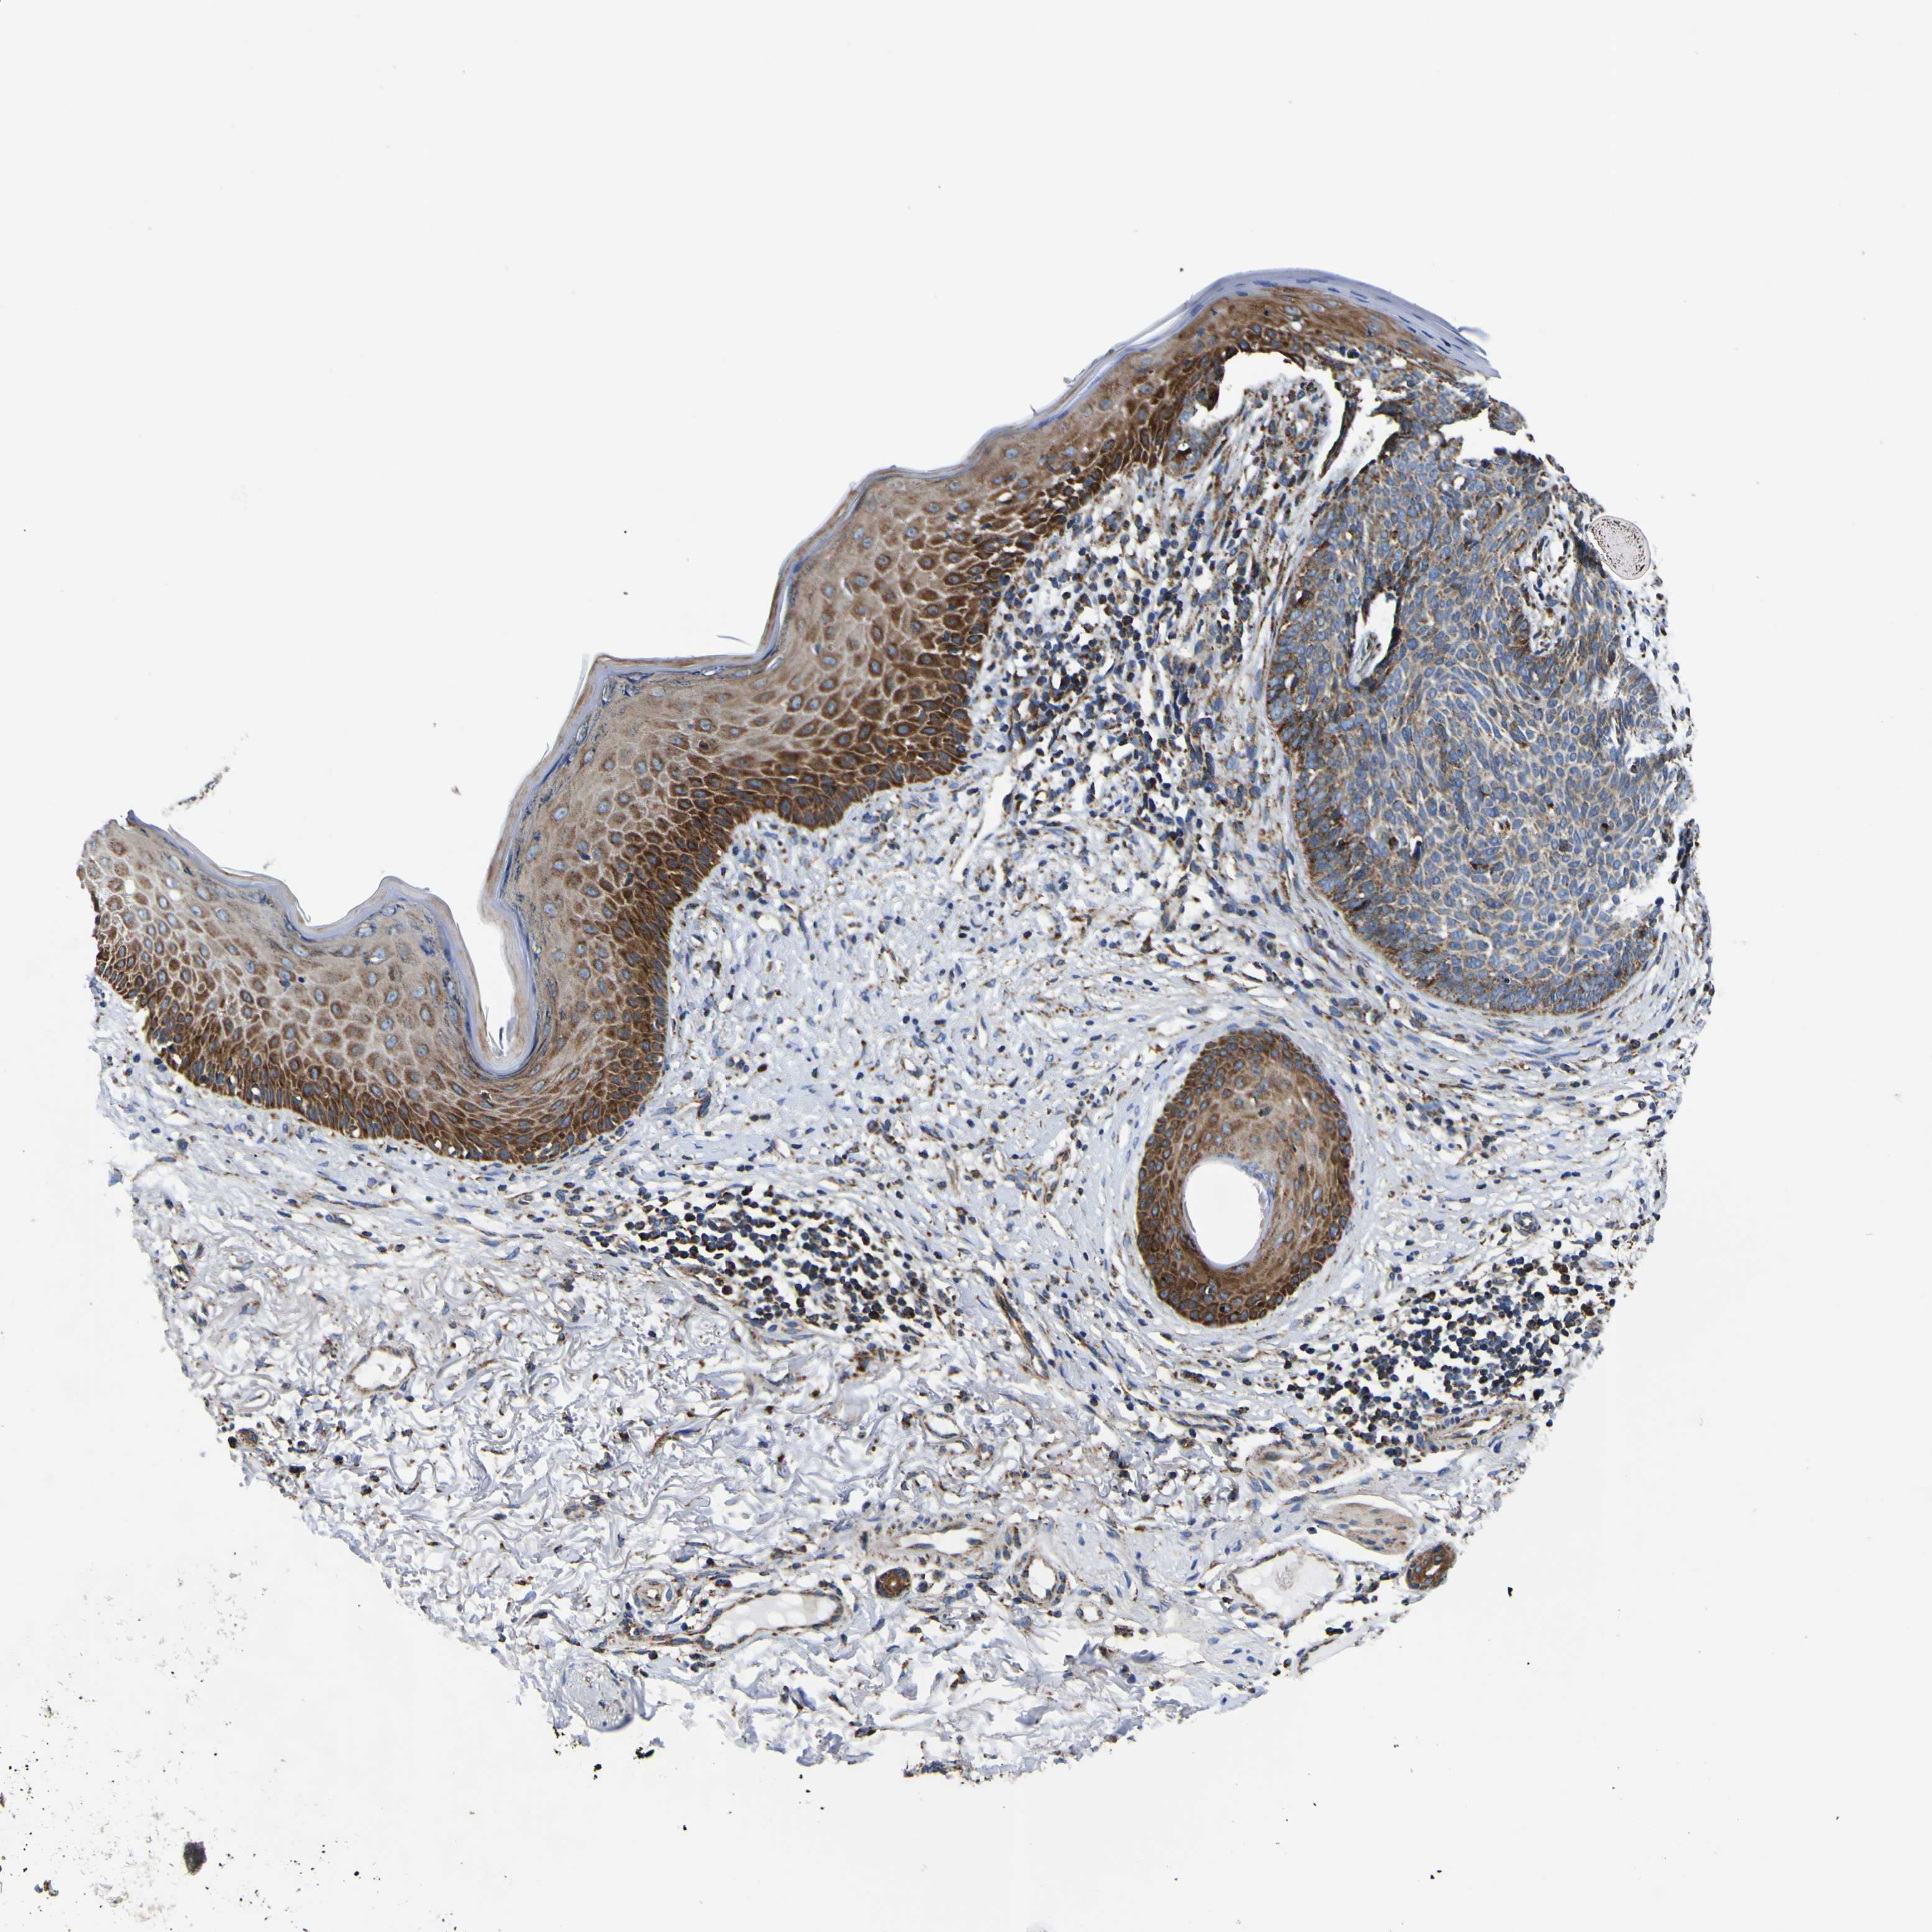

SKIN CANCER - Protein expressioni

A mouse-over function shows sample information and annotation data. Click on an image to view it in a full screen mode. Samples can be filtered based on level of antibody staining by selecting one or several of the following categories: high, medium, low and not detected. The assay and annotation is described here.

Each image is clickable and will lead to virtual microscopy that enables deeper exploration of all samples and also displays staining intensity scores, fraction scores and subcellular localization as well as patient and tissue information for each sample.

Antibody HPA012897

Staining

High

Medium

Low

Not detected

Intensity

Strong

Moderate

Weak

Negative

Quantity

>75%

75%-25%

<25%

None

Location

Nuclear

Cytoplasmic/membranous

Cytoplasmic/membranous,nuclear

Basal cell carcinoma